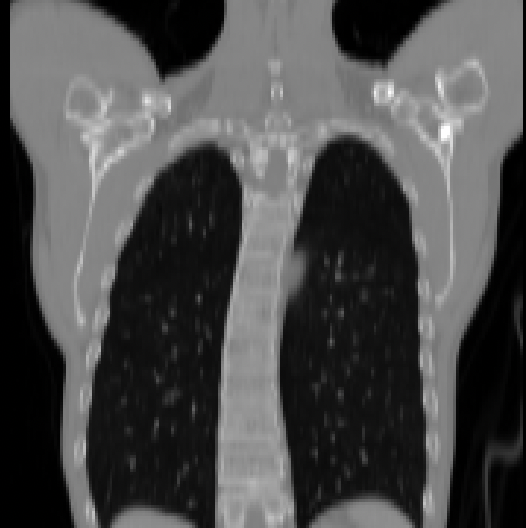

V-A2 Chest CT

A chest CT dataset of 94 subjects [61] was collected, each with a contrast-enhanced and a non-contrast scan. Each chest CT image has 35 anatomical structures manually labeled (including lung, heart, airway, esophagus, aorta, bones, muscles, arteries, and veins). We randomly split the patients into 74, 10, and 10 as training, validation, and test sets. For validation and testing, 90 image pairs are constructed for inter-patient registration, including intra-phase registration and cross-phase registration. Each image is resampled to an isotropic resolution of 2 mm and cropped to (mainly contains the chest region) by removing black borders.